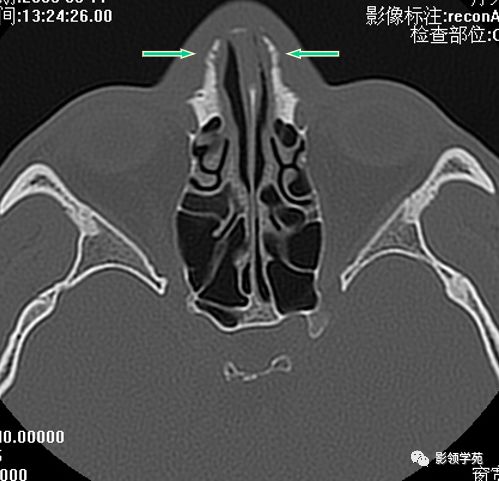

双侧鼻骨骨折

双侧上颌骨额突骨折

鼻骨间缝